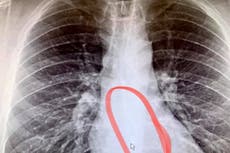

Durante décadas, los ambientalistas han estado desconcertados por el aumento de cánceres agresivos y fatales en los riñones, la próstata y la vejiga de estos animales de la costa oeste.

El estudio, que se publicó en la revista Frontiers in Marine Science, descubrió la presencia de productos químicos industriales, pesticidas y desechos de refinerías de petróleo altamente tóxicos en su grasa, lo que desencadena un virus del herpes previamente desconocido que los hace propensos a ciertos carcinomas.

Se cree que la prevalencia de estos cánceres es una de las más altas observadas en cualquier mamífero, con un 18 a 23% de los leones marinos adultos que padecieron cánceres urogenitales examinados después de su muerte durante los últimos 40 años, encontró el informe.